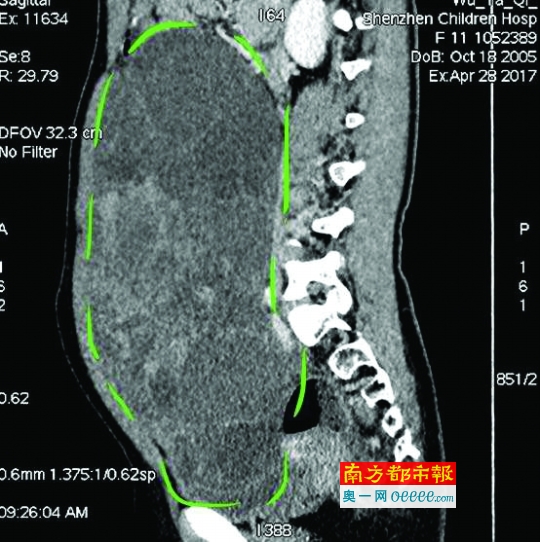

CT檢查圖像。

入院后,普外一科肖東主任向家長(zhǎng)詢問(wèn)了病史,仔細(xì)進(jìn)行了體格檢查,并完善腹部CT。CT結(jié)果提示,孩子的大部分腹腔、盆腔被一個(gè)巨大的腫瘤占據(jù),腸道、血管和腎盂都受到了不同程度的壓迫。從C T上看,腫瘤很可能起源于左側(cè)的卵巢。

手術(shù)中發(fā)現(xiàn),小琪腹中的腫瘤體積巨大,大小約為25×20×15厘米,表面光滑,來(lái)源于左側(cè)卵巢。醫(yī)生們首先將其與周圍的組織小心剝離,然后將這個(gè)占據(jù)孩子腹腔、盆腔大部分的巨大包塊完整切除,切除腫瘤后還重建了左側(cè)卵巢。剖開(kāi)瘤體,發(fā)現(xiàn)瘤體為囊性及實(shí)性混合組成,瘤體內(nèi)部充盈著粘液狀的液體,重量達(dá)到了3000克。術(shù)后小琪病情穩(wěn)定,測(cè)量腹圍從術(shù)前的72厘米減小到了62厘米。